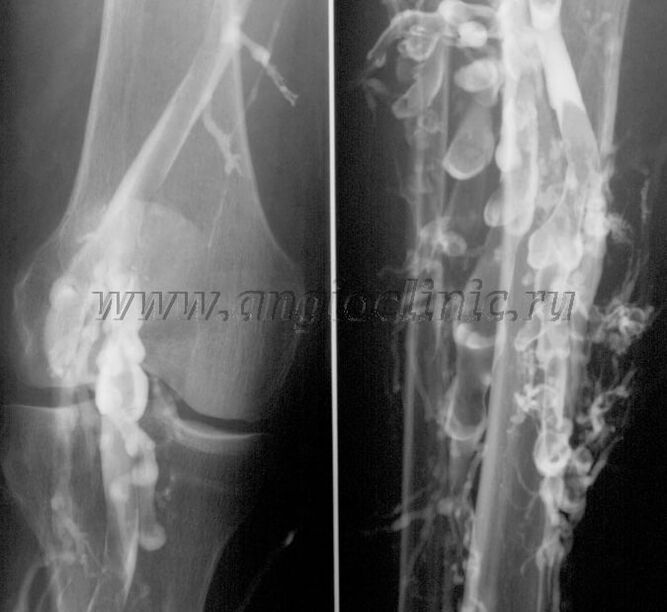

Venografi kontras

Biasanya, imbasan ultrasound adalah mencukupi untuk diagnosis penuh patologi vena, tetapi dalam beberapa kes adalah perlu untuk mengkaji hubungan antara keadaan sistem vena dalam dan dangkal, terutamanya dalam kes kambuh vena varikos dan vena varikos sekunder.

Untuk menyelesaikan masalah ini, pemeriksaan sinar-X kontras digunakan. Urat saphenous tertusuk dan kontras diberikan. Pergerakan kontras diperhatikan pada monitor mesin X-ray, dan semua ujian dan unjuran yang diperlukan dijalankan. Pada masa ini, venografi untuk urat varikos digunakan sangat jarang.